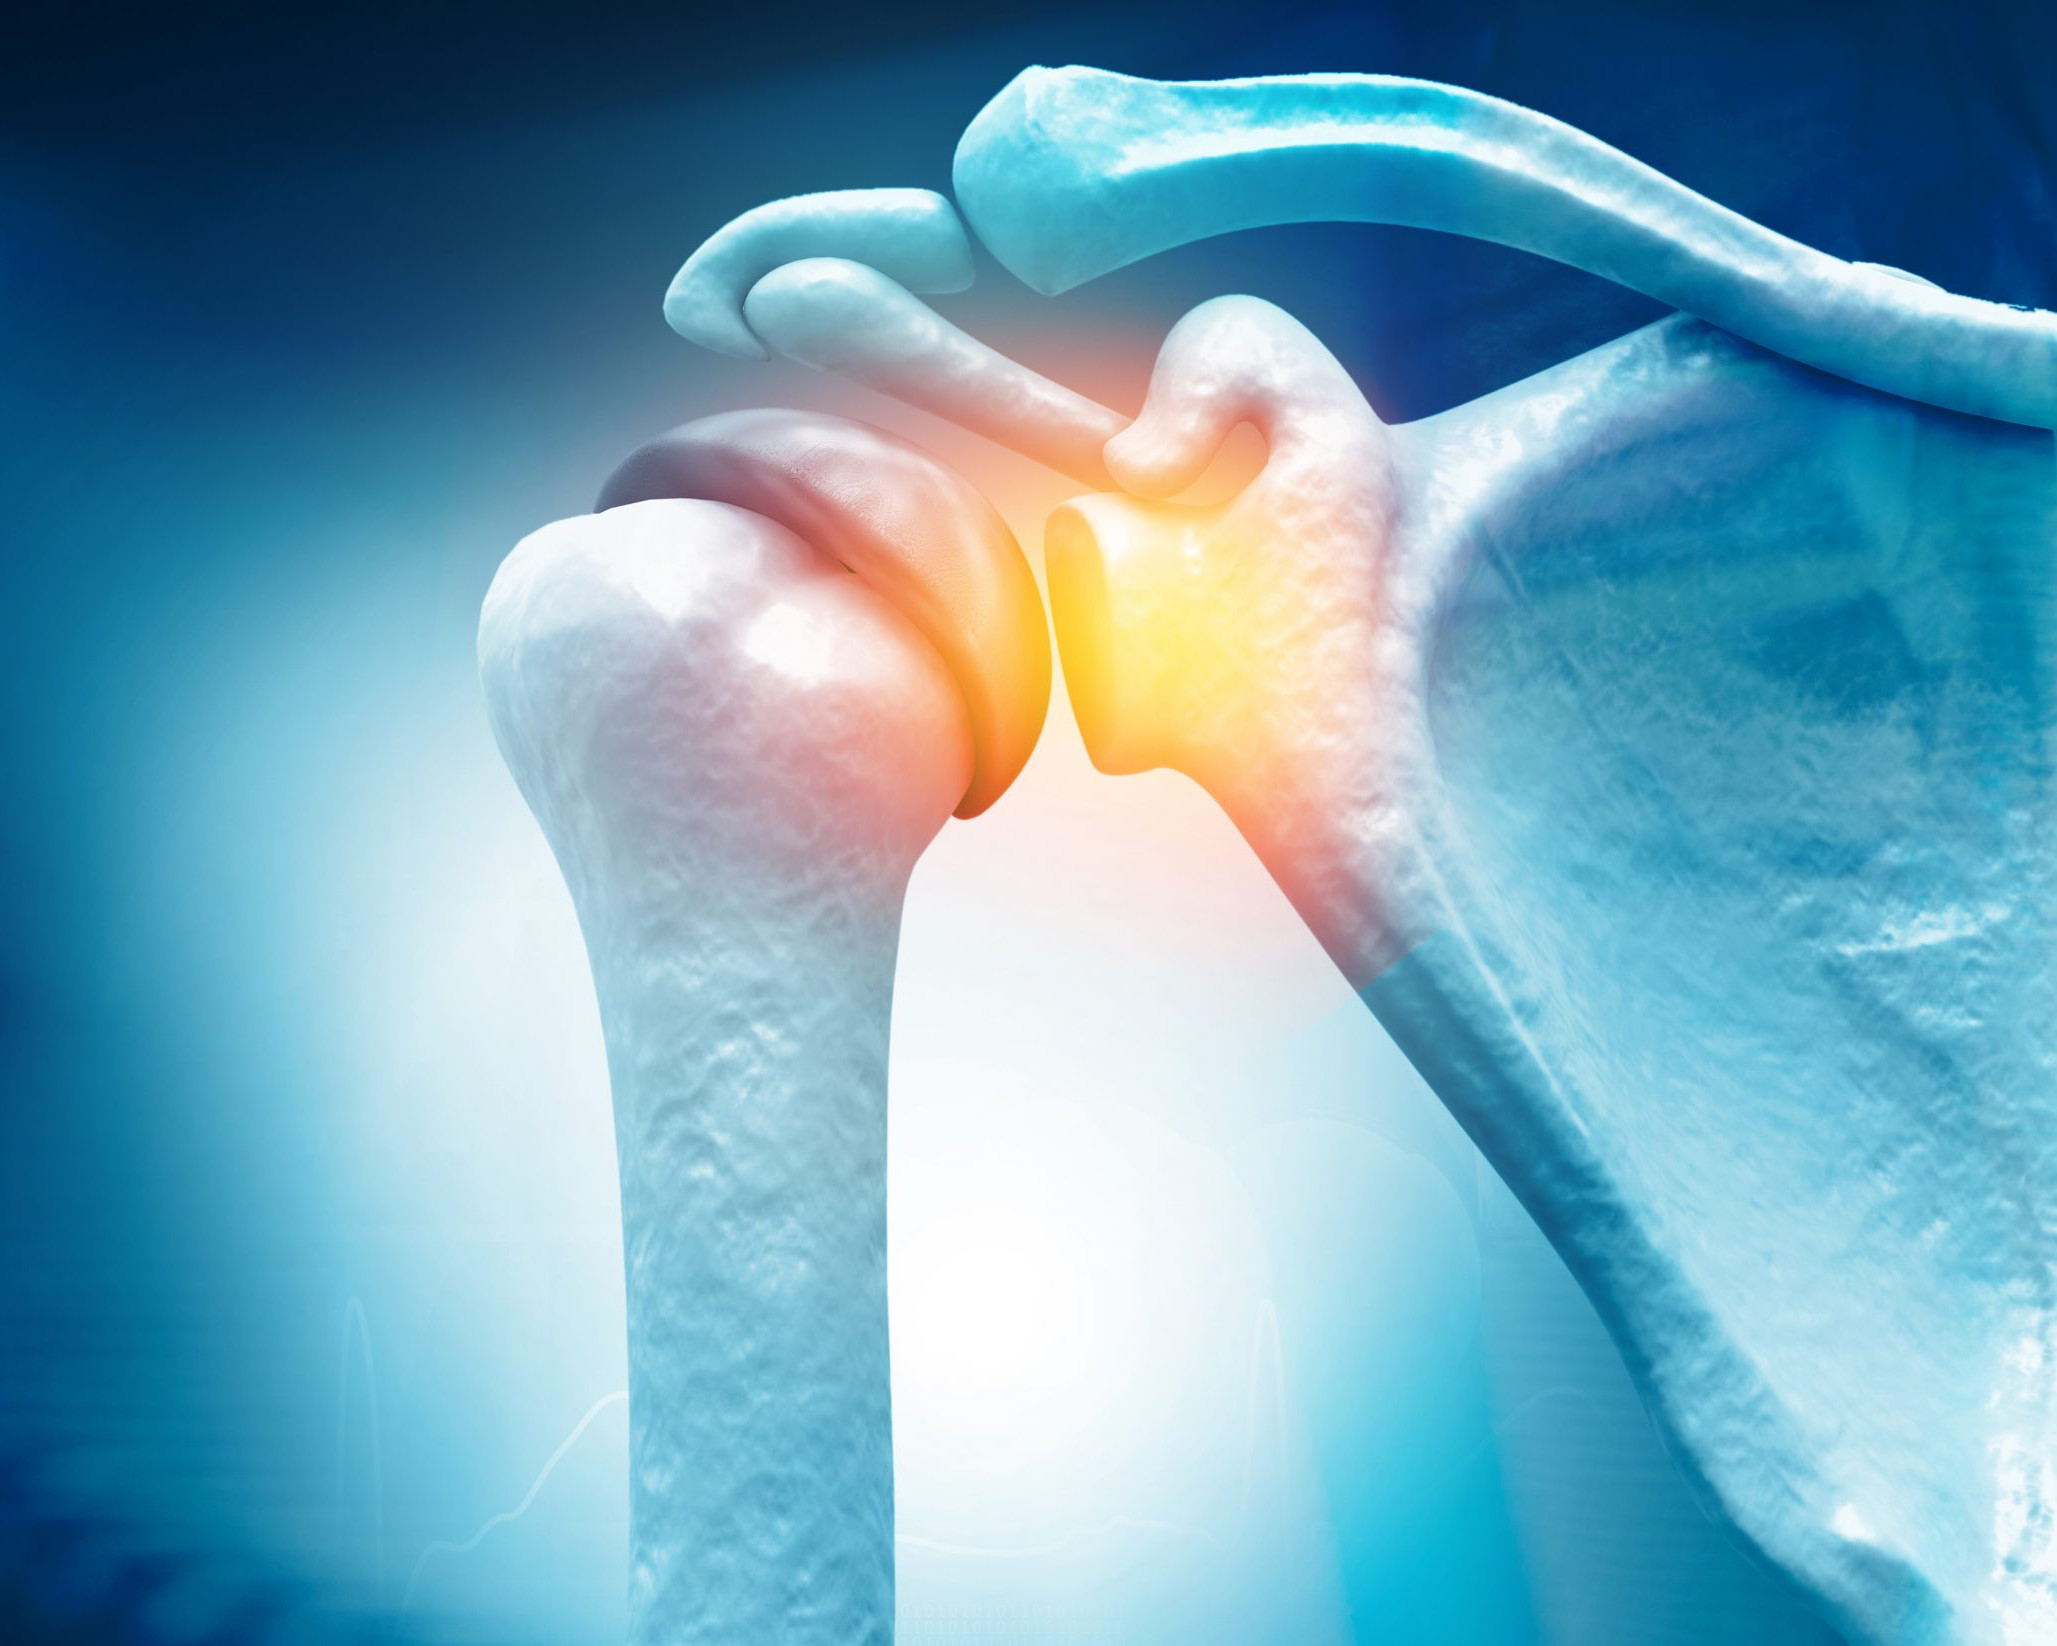

Frozen shoulder is a common condition estimated to affect 2%-5% of the population (Hand, 2008). It is often a condition that develops gradually, and its main feature is of stiffness and pain. The joint that is affected is the glenohumeral joint (from Greek glene which means eyeball, and –oid, refers to ” the form or shape “) i.e. shape of an eyeball. Looking at the image of the skeleton, you can clearly see that shape and form wise, the name makes sense! This is the joint between the humerus (your upper arm bone) and the scapula (shoulder blade).